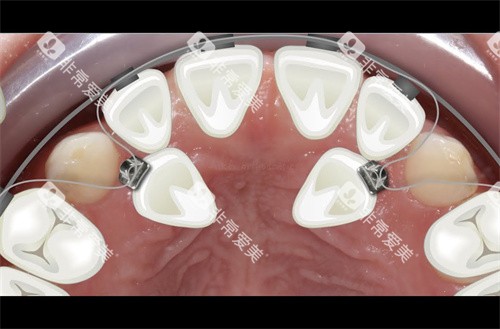

正畸项目:

金属托槽矫正:12000-18000元

陶瓷托槽矫正:15000-22000元

隐形矫正:25000-40000元